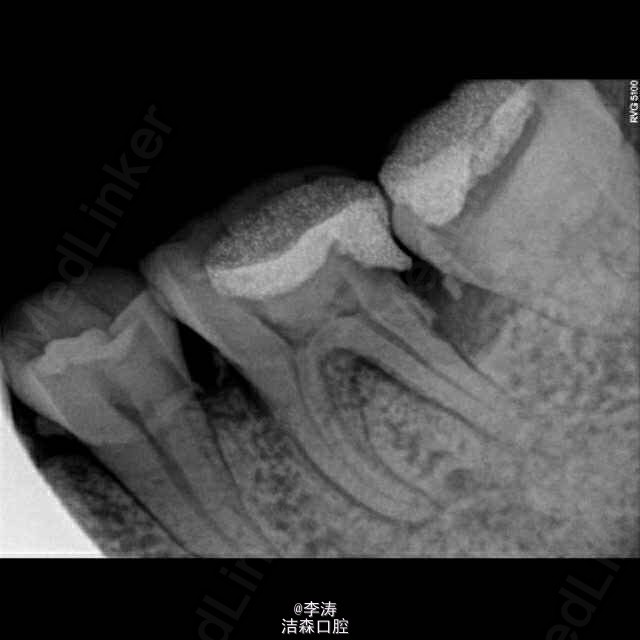

根管预备形成台阶1例

36牙根管治疗,近中根略弯曲,先疏通至15号,k3冠向下法预备,预备时形成台阶,然后怎么预弯都下不去! 太弯根管的还是应该使用手扩,特别是k3,弯曲根管尽量不用,容易形成台阶。另外预备过程中不能使用暴力!!